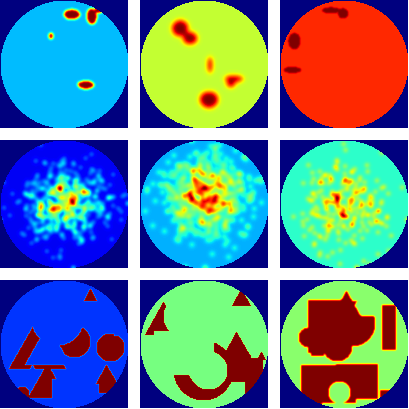

where NP𝑁𝑃N\,P is the number of projection angles, in this case, 128 projections, equally spaced in 360 degrees, and NR𝑁𝑅N\,R is the number of bin measurements per projection angle. The acquired sinograms were additionally randomised with a Poisson probability distribution to provide the noisy sets of projections. Three levels of Poisson noise was used by scaling the values of the sinograms to 90%, 50%, and 10%, as Low, Medium and High noise. Examples of the random phantom generated can be found in figure 1

Refer to caption

Figure 1: Random samples of the generated images used to train the CNNR proposed method